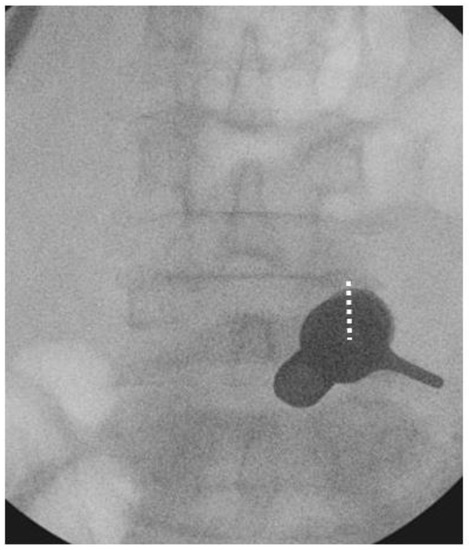

We performed the procedure under general anesthesia. The patient was positioned in a prone position on a Wilson Frame over a radiolucent operating table with the spine in slight flexion. The endoscopic procedure was performed with an irrigation fluid pressure of 25–40 mmHg using an irrigation pump. We stood on the symptomatic side and used the upper pedicle screw skin incision for the uniportal endoscope insertion and docking for each corresponding level of posterolateral approach interbody fusion. For example, we used the skin incision over the right L4 pedicle on the AP intraoperative fluoroscopic image to perform right L4/5 Endo-TLIF (Figure 5) We incised a 1.6 cm skin incision to facilitate working cannula placement and made an extended fascia incision of 3 cm to allow mobility of the working channel and subsequent rod placement after completion of interbody cage insertion. We performed the insertion of the cage(s) prior to pedicle screw insertion.

Figure 5. Docking position of right L4/5 Endo-TLIF. The incision was made over the right L4 pedicle (dotted white line) and the working cannula was docked on the pars interarticularlis of right L4/5.

Brainsci 10 00373 g005